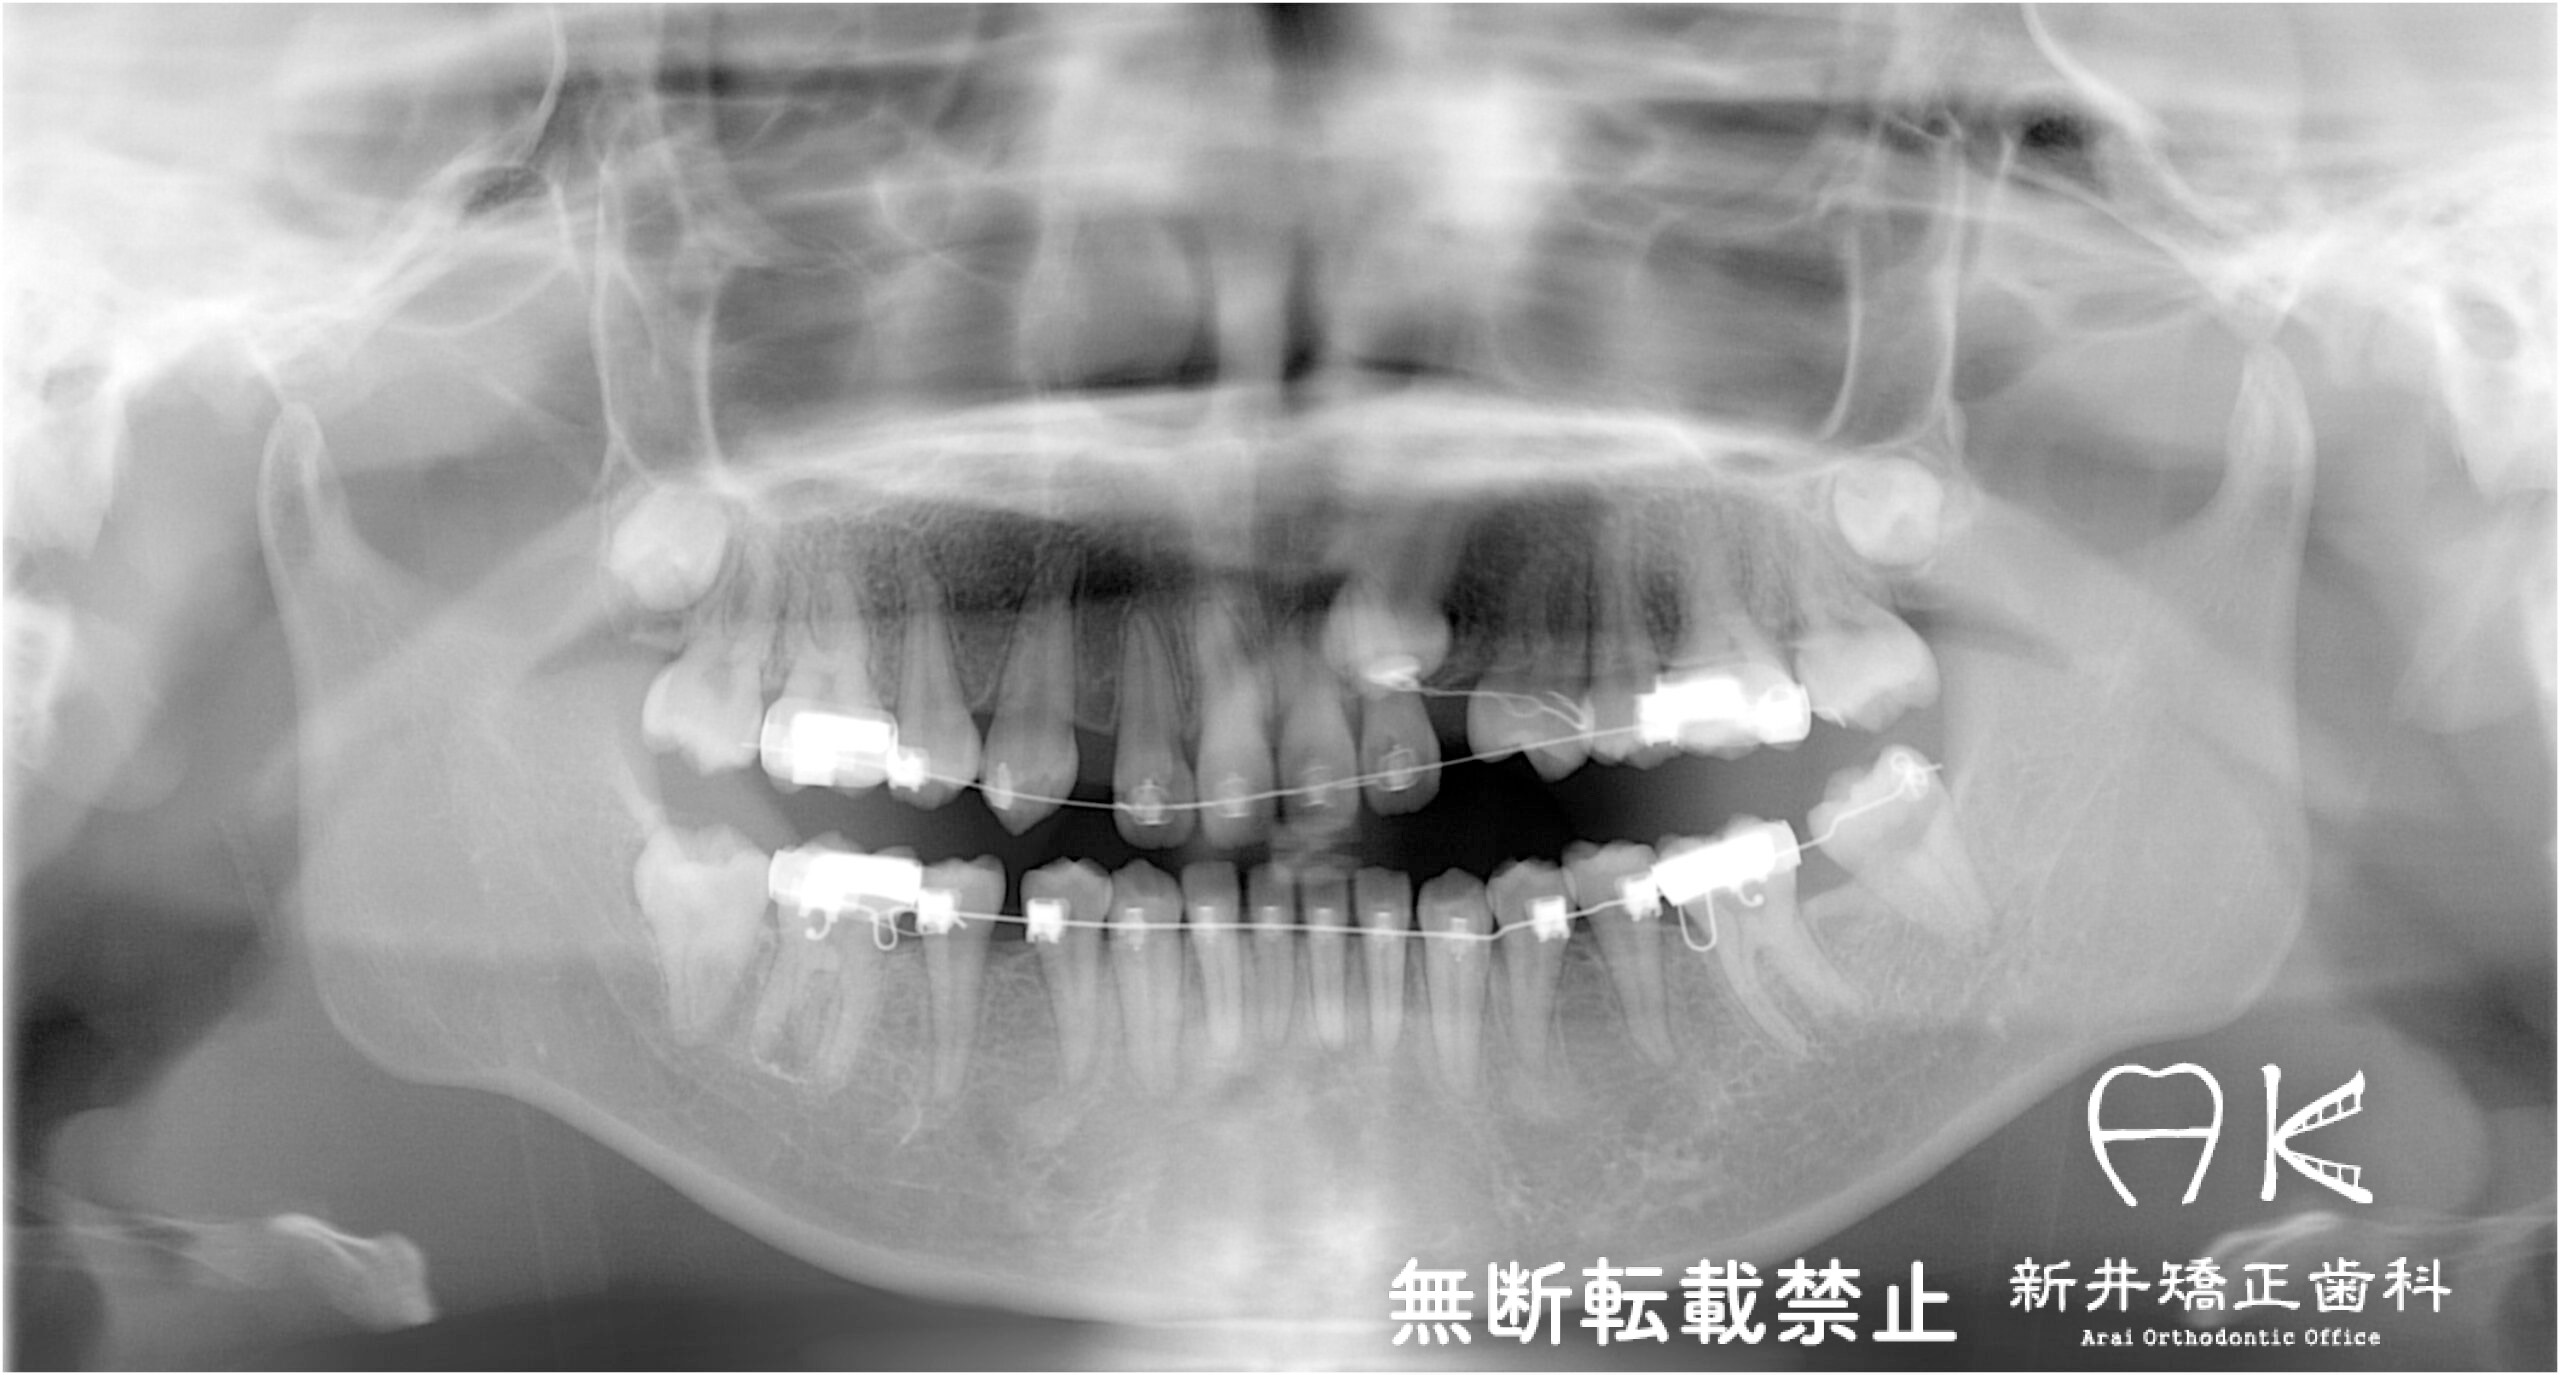

治療中

治療内容

| 抜歯の有無 | 上下左右第一小臼歯(前から4番目の歯) 上下左右第三大臼歯(親知らず) |

| 使用矯正装置 | セルフライゲーションリンガルブラケット セルフライゲーションブラケット(セラミッククリッピー) 歯科矯正用アンカースクリュー |

治療前後の解説

| 治療前 | でこぼこしている歯による歯磨きのやりにくさや、奥歯がしっかり咬んでいない鋏状咬合(すれ違い咬合)。 出っ歯による口の閉じにくさ(口唇閉鎖不全)と、正面から見た時のオトガイ部にできる梅干し様のシワやイーラインから飛び出た口元(口ゴボ)。 機能面も審美面も気にしていた患者さんです。 治療中もなるべく装置を目立たせたくないため、ハーフリンガルでの治療となりました。 |

| 治療後 | 上下の歯がお互いにはまり込み、全体的に緊密な咬み合わせになっています。 出っ歯が治り、口元の突出感が改善されて綺麗なEラインを獲得しました。 すれ違い咬合や叢生(歯のでこぼこ)も治って歯磨きがしやすく、嚙みやすい状態になっています。 |